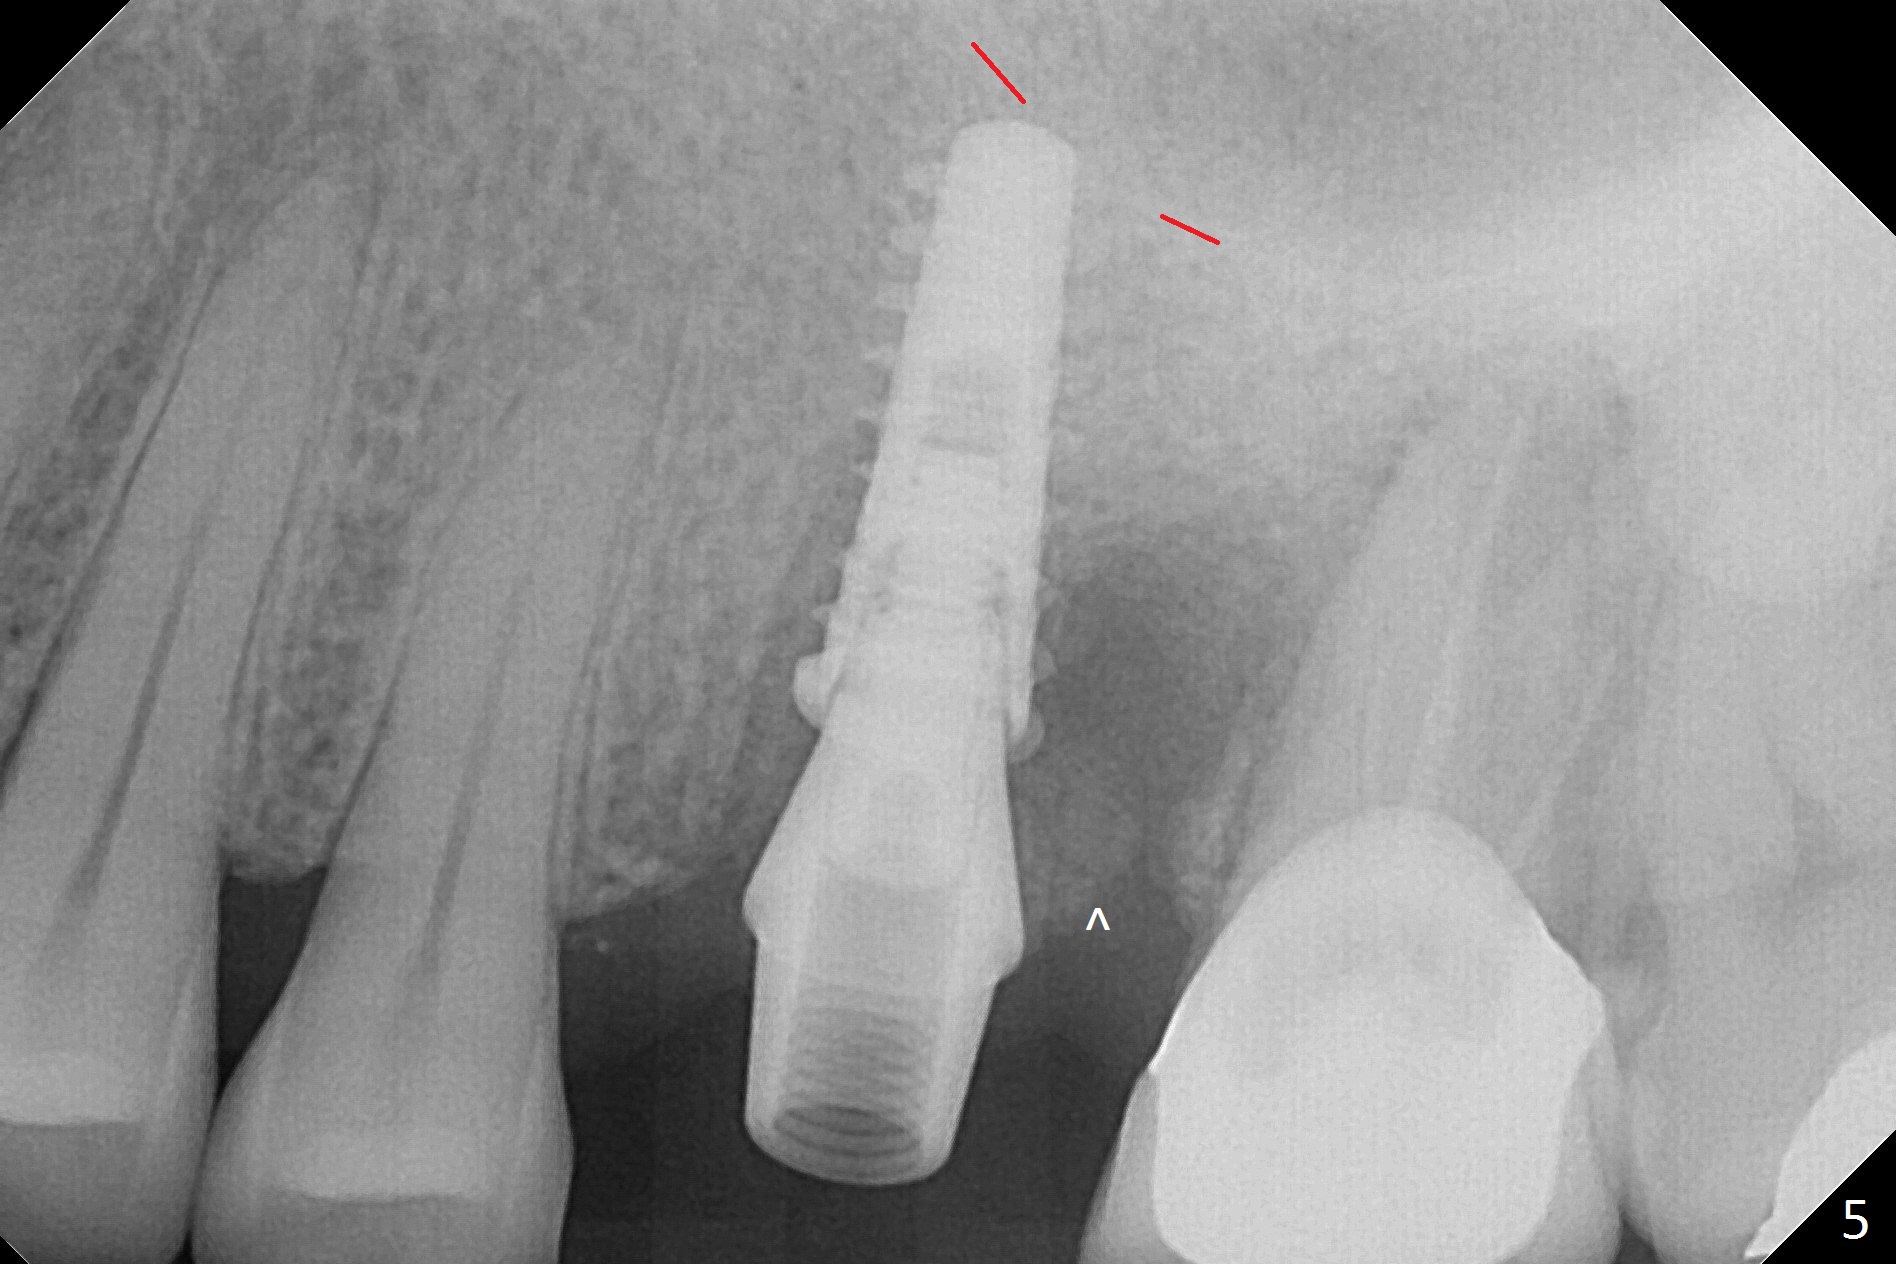

Magic Split is used to start access (flapless) and initial bone expansion at #14. The split does not go deep, since bone density is high in the deep portion. A 1.6 mm drill has to be used for 13 mm (Fig.1). Note the low bone density in the distobuccal socket (*). Later the osteotomy extends to 15 mm (gingival level). After 3.8 mm Magic Drill (MD) for 15 mm, a 4x11 mm dummy implant is placed with insertion torque of 60 Ncm (implant motor, Fig.2). After 4.3 mm MD, a 4.5x11 mm IBS implant is placed with insertion torque of 60 Ncm for implant motor >40 Ncm for torque wrench (Fig.3). The implant seems to be placed deep, but the buccal plate feels to be low. Following bone graft buccally, especially distobuccal (Fig.4,5 ^), a 5x4(3) mm abutment is placed. The buccal gingiva is torn during bone graft (Fig.6 >). Periodontal dressing is applied around the abutment (for increased retention) for wound protection.